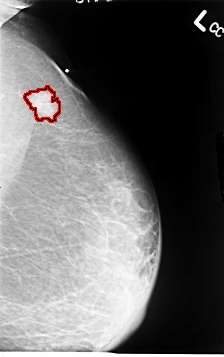

B_3064_1.RIGHT_MLO

FILE: B_3064_1.LEFT_MLO.OVERLAY

TOTAL_ABNORMALITIES 1

ABNORMALITY 1

LESION_TYPE MASS SHAPE IRREGULAR MARGINS SPICULATED

ASSESSMENT 5

SUBTLETY 5

PATHOLOGY MALIGNANT

TOTAL_OUTLINES 1

BOUNDARY